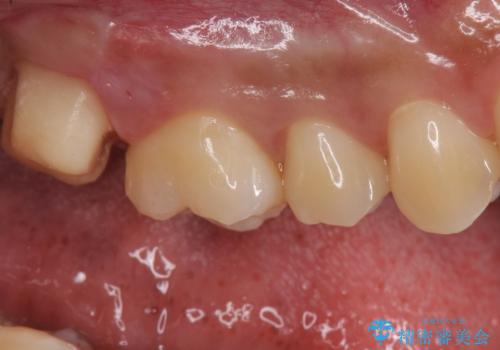

銀歯をなくしたい ジルコニアクラウンでの修復

- 銀歯を白くしたいとのことで来院されました。

歯を覆っている銀の詰め物の面積が広く、セラミックで同じ形態にすると強度に不安が残るため被せ物での修復処置を行っていきます。

ブラッシングが上手な患者様であったため歯茎の締りもよく、大変適合の良い被せ物を装着することができました。